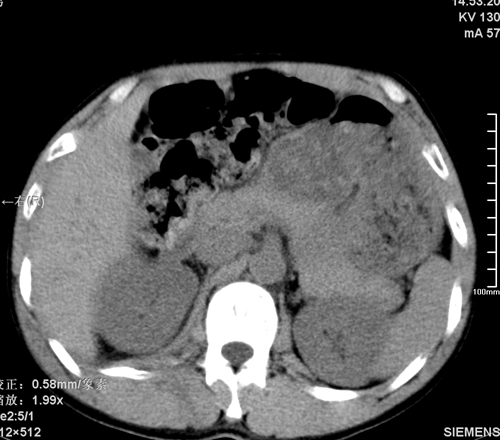

以下是引用tao772在2008-3-28 12:29:00的发言:[br]右侧腹膜后积血,右侧腰大肌挫伤,右侧部分横突骨折. 肾脏最好报一下挫伤,必要时增强。